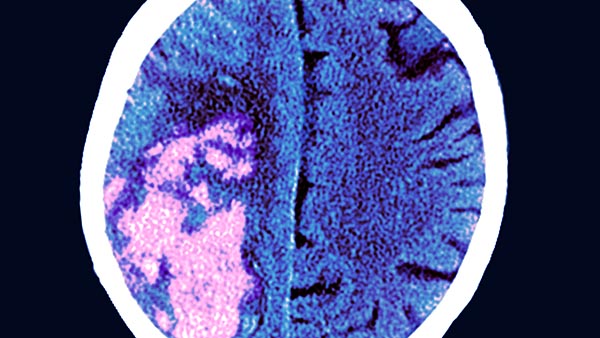

The University Hospital Radiology Clinic vascular neurointerventional service provides patient consultations on an array of conditions of the central and peripheral nervous systems, including stroke and aneurism.